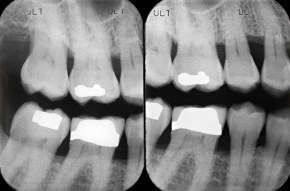

Along with a dental examination dental x-rays are an important part of your dental health. Dental x-rays help your dentist diagnose cavities (that can not be seen by a visual examination), cracks in the tooth, diseases in the bone, periodontal or gum disease, infections underneath the gum, bone loss, abscesses, cysts or tumors.

X-rays can help diagnose problems early, when they are easily treatable and cost a lot less money. It is better to have a small filling done then to let it go until you are in pain. If there is pain or infection this means you have let the problem get too far and may need a lot of treatment which also increases time of treatment and cost.